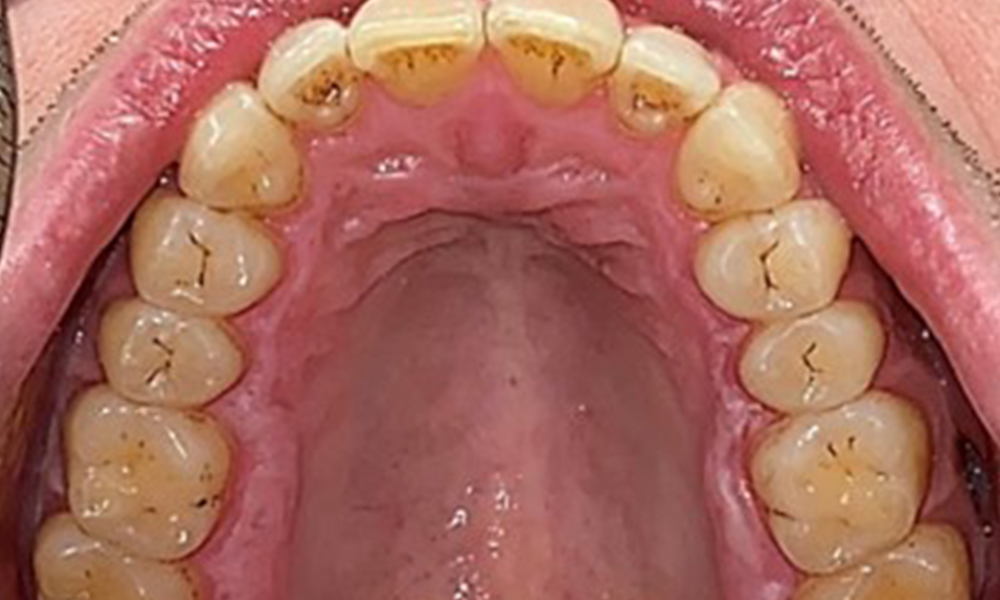

Vue occlusale du maxillaire.

Fig. 3: Vue occlusale du maxillaire, © Dr R. Krapf

Vue occlusale de la mandibule.

Fig. 4: Vue occlusale de la mandibule, © Dr R. Krapf

Résultats extra-oraux et intra-oraux

Il n'y a pas eu de résultats pathologiques extra-oraux. Lors de l'examen intrabuccal, l'inspection de la vue frontale a révélé une décoloration brunâtre près de la gencive kératinisée et à la transition vers la muqueuse mobile (Fig. 2), qui pourrait être attribuée à la consommation de nicotine. Des lésions blanchâtres de la muqueuse ont été observées sur le palais, en particulier près des surfaces palatines des molaires maxillaires, ce qui indique une kératinisation accrue et peut également être attribué à la consommation de nicotine. La langue était recouverte d'un enduit amovible blanc et brunâtre.

Résultats dentaires

Le patient a une dentition complète avec un total de 28 dents. Il y avait des érosions et des attritions notables. (Fig. 4, Fig. 5). En raison du bruxisme, le patient a porté pendant de nombreuses années une attelle avec une gouttière ajustée la nuit. Les érosions ont été causées par une consommation prolongée de boissons isotoniques. Aucune perte d'os parodontal ou carie active n'a été observée.